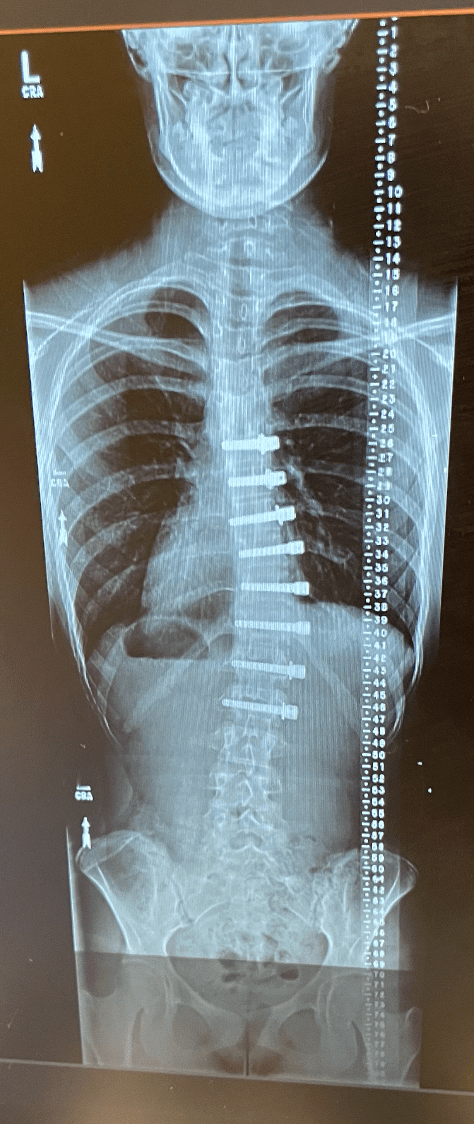

My X-Rays – My Scoliosis Journey